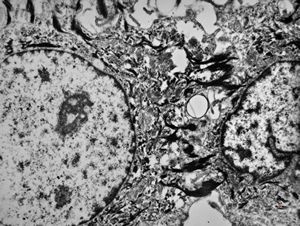

F,41y. | synovial metaplasia - capsule of implantate